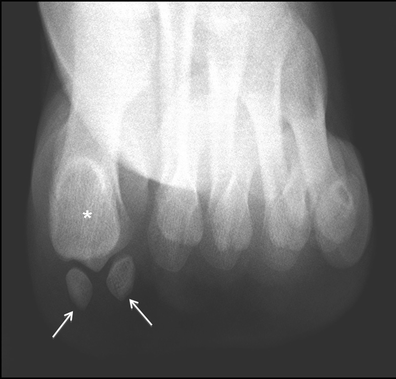

Degeneration at a synchondrosis. a Long-axis axial CT image shows an apparently normal type II accessory navicular (arrow) with a preserved synchondrosis with the navicular tubercle. b In comparison, this long-axis axial CT image of a different foot depicts increased sclerosis and fragmentation of a type II accessory navicular (white arrow) and fragmentation of the navicular tubercle at the synchondrosis (black arrow) consistent with degenerative change

Degeneration at a synchondrosis. a Long-axis axial CT image shows increased sclerosis (black arrow) and subchondral cyst formation in an os trigonum. b Sagittal CT image reveals subchondral cyst formation in the talus (black arrow) and os trigonum (white arrow) across the synchondrosis, due to degenerative change